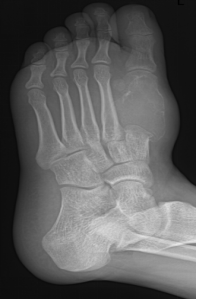

75Y,M

手足短骨解剖及常见疾病的影像学表现